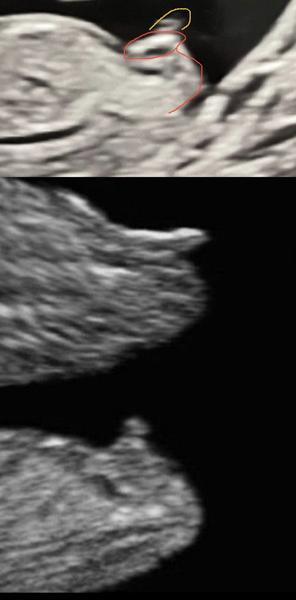

Holky, tak mi ještě psala jedna paní, že na to koukáme špatně. Dle jejího je to jasná holka, protože to červené je výběžek a to žluté už bude šňůra nebo končetina.

Tak, když to přiblížim, tak to tam opravdu vidím, opravdu budeme muset počkat do další kontroly. Ale je to zábava, sdílím, protože to je opravdu jako věštění z kávové sedliny 🤣🤣🤣